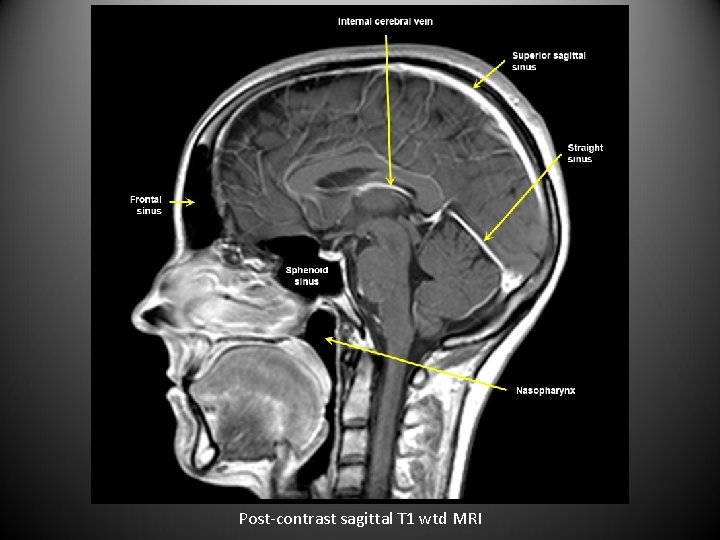

Post-contrast sagittal T 1 wtd MRI